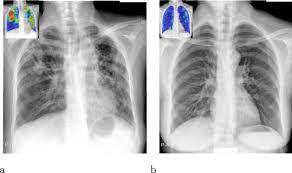

Tuberculosis without established localization the greatest difficulties arise at diagnosing tubercular intoxication and small formsof lymphatic nodes. From point ai to point tb: The samples are tested for tb bacteria. Abnormalities on chest radiographs may be suggestive of, but are never diagnostic of tb, but can be used to rule out pulmonary tb. Case contributed by dr brenda lee solorzano frontal chest x ray shows bilateral micronodular insterstitial effusion. For decades, tuberculosis (tb), a potentially serious infectious lung disease, continues to be a leading cause of worldwide death. From tb suspects attending a chest clinic in nairobi, kenya, three sputum specimens were examined for zn and culture (lowenstein jensen). On radiograph tubercular lesions of lung parenxyma, stroma comes to light as shadows (densities, consolidations).

A practical manual for preventing tb, 2011. Tuberculosis without established localization the greatest difficulties arise at diagnosing tubercular intoxication and small formsof lymphatic nodes. The samples are tested for tb bacteria. Tuberculosis of intrathoracic lymphatic nodes 3.2.3. Tb is an airborne disease caused by the bacteria mycobacterium tuberculosis and mycobacterium bovis. Case contributed by dr brenda lee solorzano frontal chest x ray shows bilateral micronodular insterstitial effusion. On radiograph tubercular lesions of lung parenxyma, stroma comes to light as shadows (densities, consolidations). From tb suspects attending a chest clinic in nairobi, kenya, three sputum specimens were examined for zn and culture (lowenstein jensen). Thus chest x rays are neither specific nor sensitive and so remain a supplement to microbiological tests such as microscopy pcr and culture. Culture was used as gold standard. Tuberculosis a manual for medical students. Left apical bronchiectasis at the level of. At the description of these shadows it is.

Abnormalities on chest radiographs may be suggestive of, but are never diagnostic of tb, but can be used to rule out pulmonary tb. At the description of these shadows it is. Thus chest x rays are neither specific nor sensitive and so remain a supplement to microbiological tests such as microscopy pcr and culture. This manual would not have been possible without the comments and suggestions of colleagues with considerable. Tuberculosis is an infectious disease that causes inflammation, the formation of tubercles and other growths within tissue, and can cause tissue death. From tb suspects attending a chest clinic in nairobi, kenya, three sputum specimens were examined for zn and culture (lowenstein jensen). Therefore, all persons with chest radiographic findings suggestive of tb. Case contributed by dr brenda lee solorzano frontal chest x ray shows bilateral micronodular insterstitial effusion. On radiograph tubercular lesions of lung parenxyma, stroma comes to light as shadows (densities, consolidations). Read about the history of tuberculosis (tb), its symptoms, causes, diagnosis, treatment. A practical manual for preventing tb, 2011. The contagious disease of tuberculosis not only attacks the lungs but also can affect other organs such as the kidney, spine and brain. From point ai to point tb: